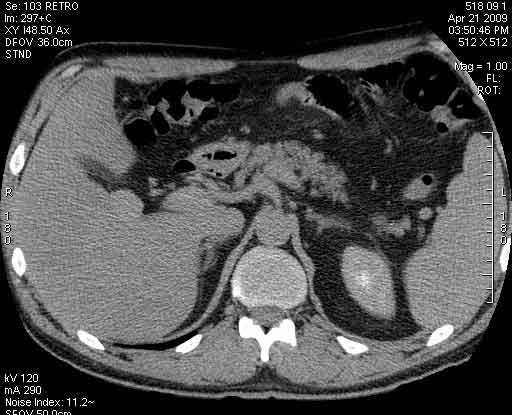

Пациент с клиникой острого холецистита на фоне ЖКБ.

Сонограммы, КТ- артериальная, портальная и отсроченная паренхиматозная фазы

Сделали КТ (весьма похвальная тактика); по КТ: в артериальную фазу: периферическое усиление в виде сливающихся островков контраста, с центрипетальной направленностью. Венозная и отсроченная фаза-хорошее накопление контраста; образование практически изоденсно по отношению к паренхиме печени. Классика гемангиомы. Вуаля-диагноз на "тарелочке".